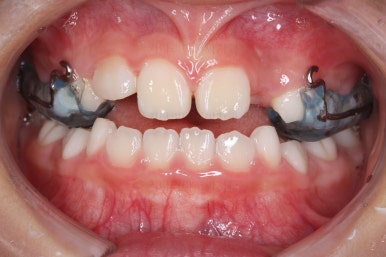

치료 시작 3개월째의 모습입니다.

윗니가 점점 앞으로 나오는게 보이실거에요. 사실은 치아가 나오는 것이 아니라 치아가 담겨있는 위턱뼈가 통째로 앞으로 나온 것입니다.

좀 더 하면 마무리를 할 수 있을 것 같네요.

치료 시작 10개월만에 거꾸로 물리는건 개선이 되었습니다.

페이스마스크 치료는 종료했습니다.